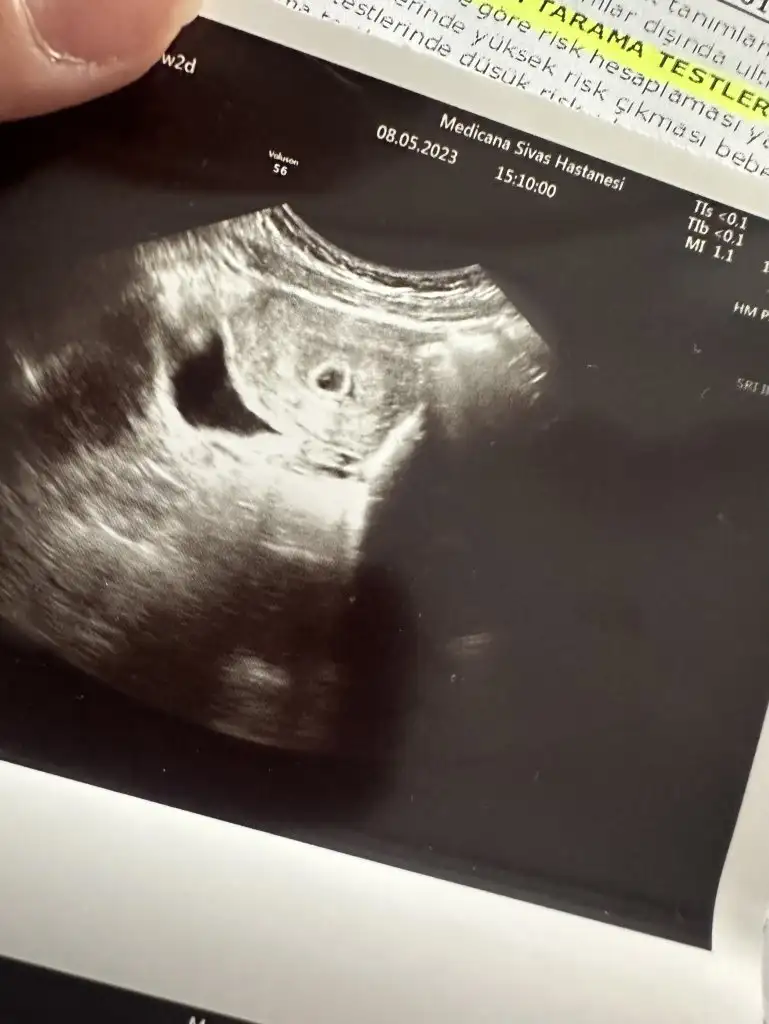

Merhaba kızlar, uzun zamandır bebek tedavisi görüyorduk.Aşılama, tüp bebek denedik olmamıştı.Yumurta rezervim çok azdı.FSH yüksekti.Umudumu kaybettiğim anda bu ay hamile olduğumu öğrendim.Hala çok şaşkınım.SAT 3 Nisan.3 Mayıs'ta kan testi vermiştim hafif lekelenme olduğu için çıkmayacağını düşünüyordum.Sonucu bile almaya gitmedim.E-nabızda Beta hcg 1137 görünce inanamadım.

Cumartesi günü kese çok küçük göründü.Yarin kontrolüm var.Insallah hepimiz sağlıklı bir gebelik dönemi geçiririz.Hepinize hayırlı olsun.Rabbim sağlıklı bir şekilde bebeklerimizi kucağımıza almak nasip eder inşallah.